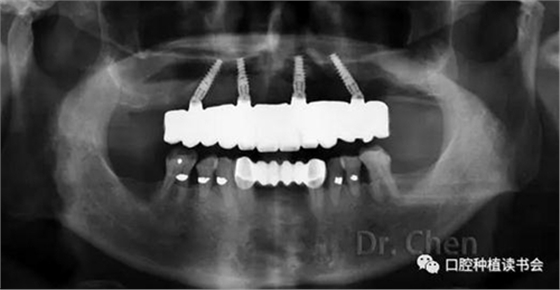

曲斷片顯示所有氧化鋯接口與Multi-unit基臺(tái)之間完全就位,骨水平穩(wěn)定于植體頸部(圖13)。

患者佩戴永久修復(fù)體后半年復(fù)診,咀嚼功能及美觀、發(fā)音均滿意。骨水平穩(wěn)定,無機(jī)械及生物學(xué)并發(fā)癥。

▲ 永久修復(fù)后的曲斷片